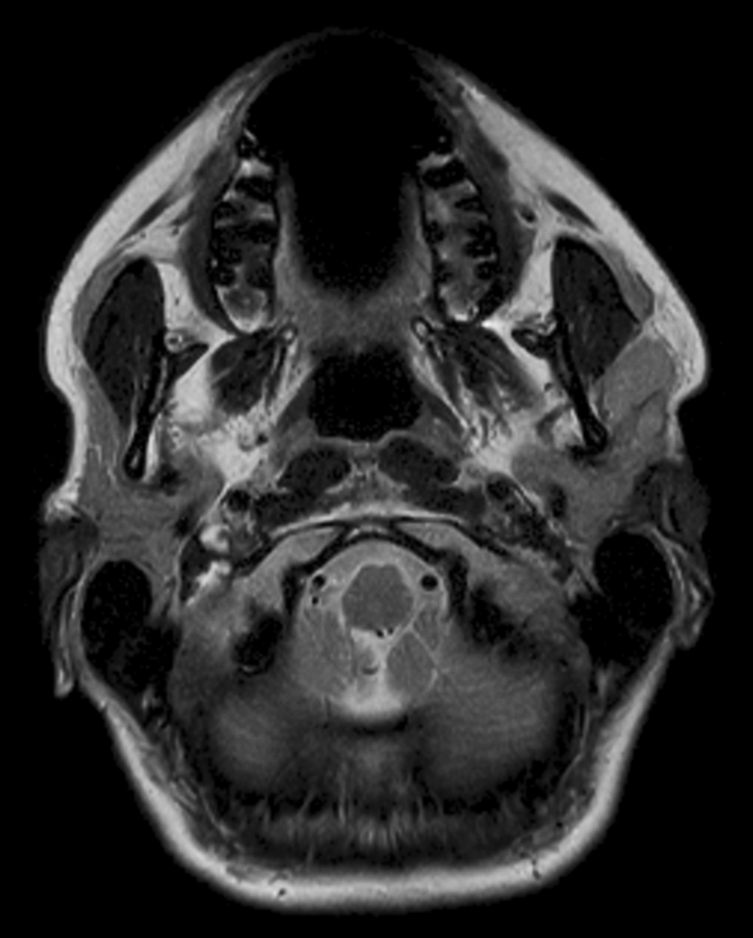

Axial T2w TSE

Axial T1w TSE

Axial T1w  mDIXON TSE (In Phase)